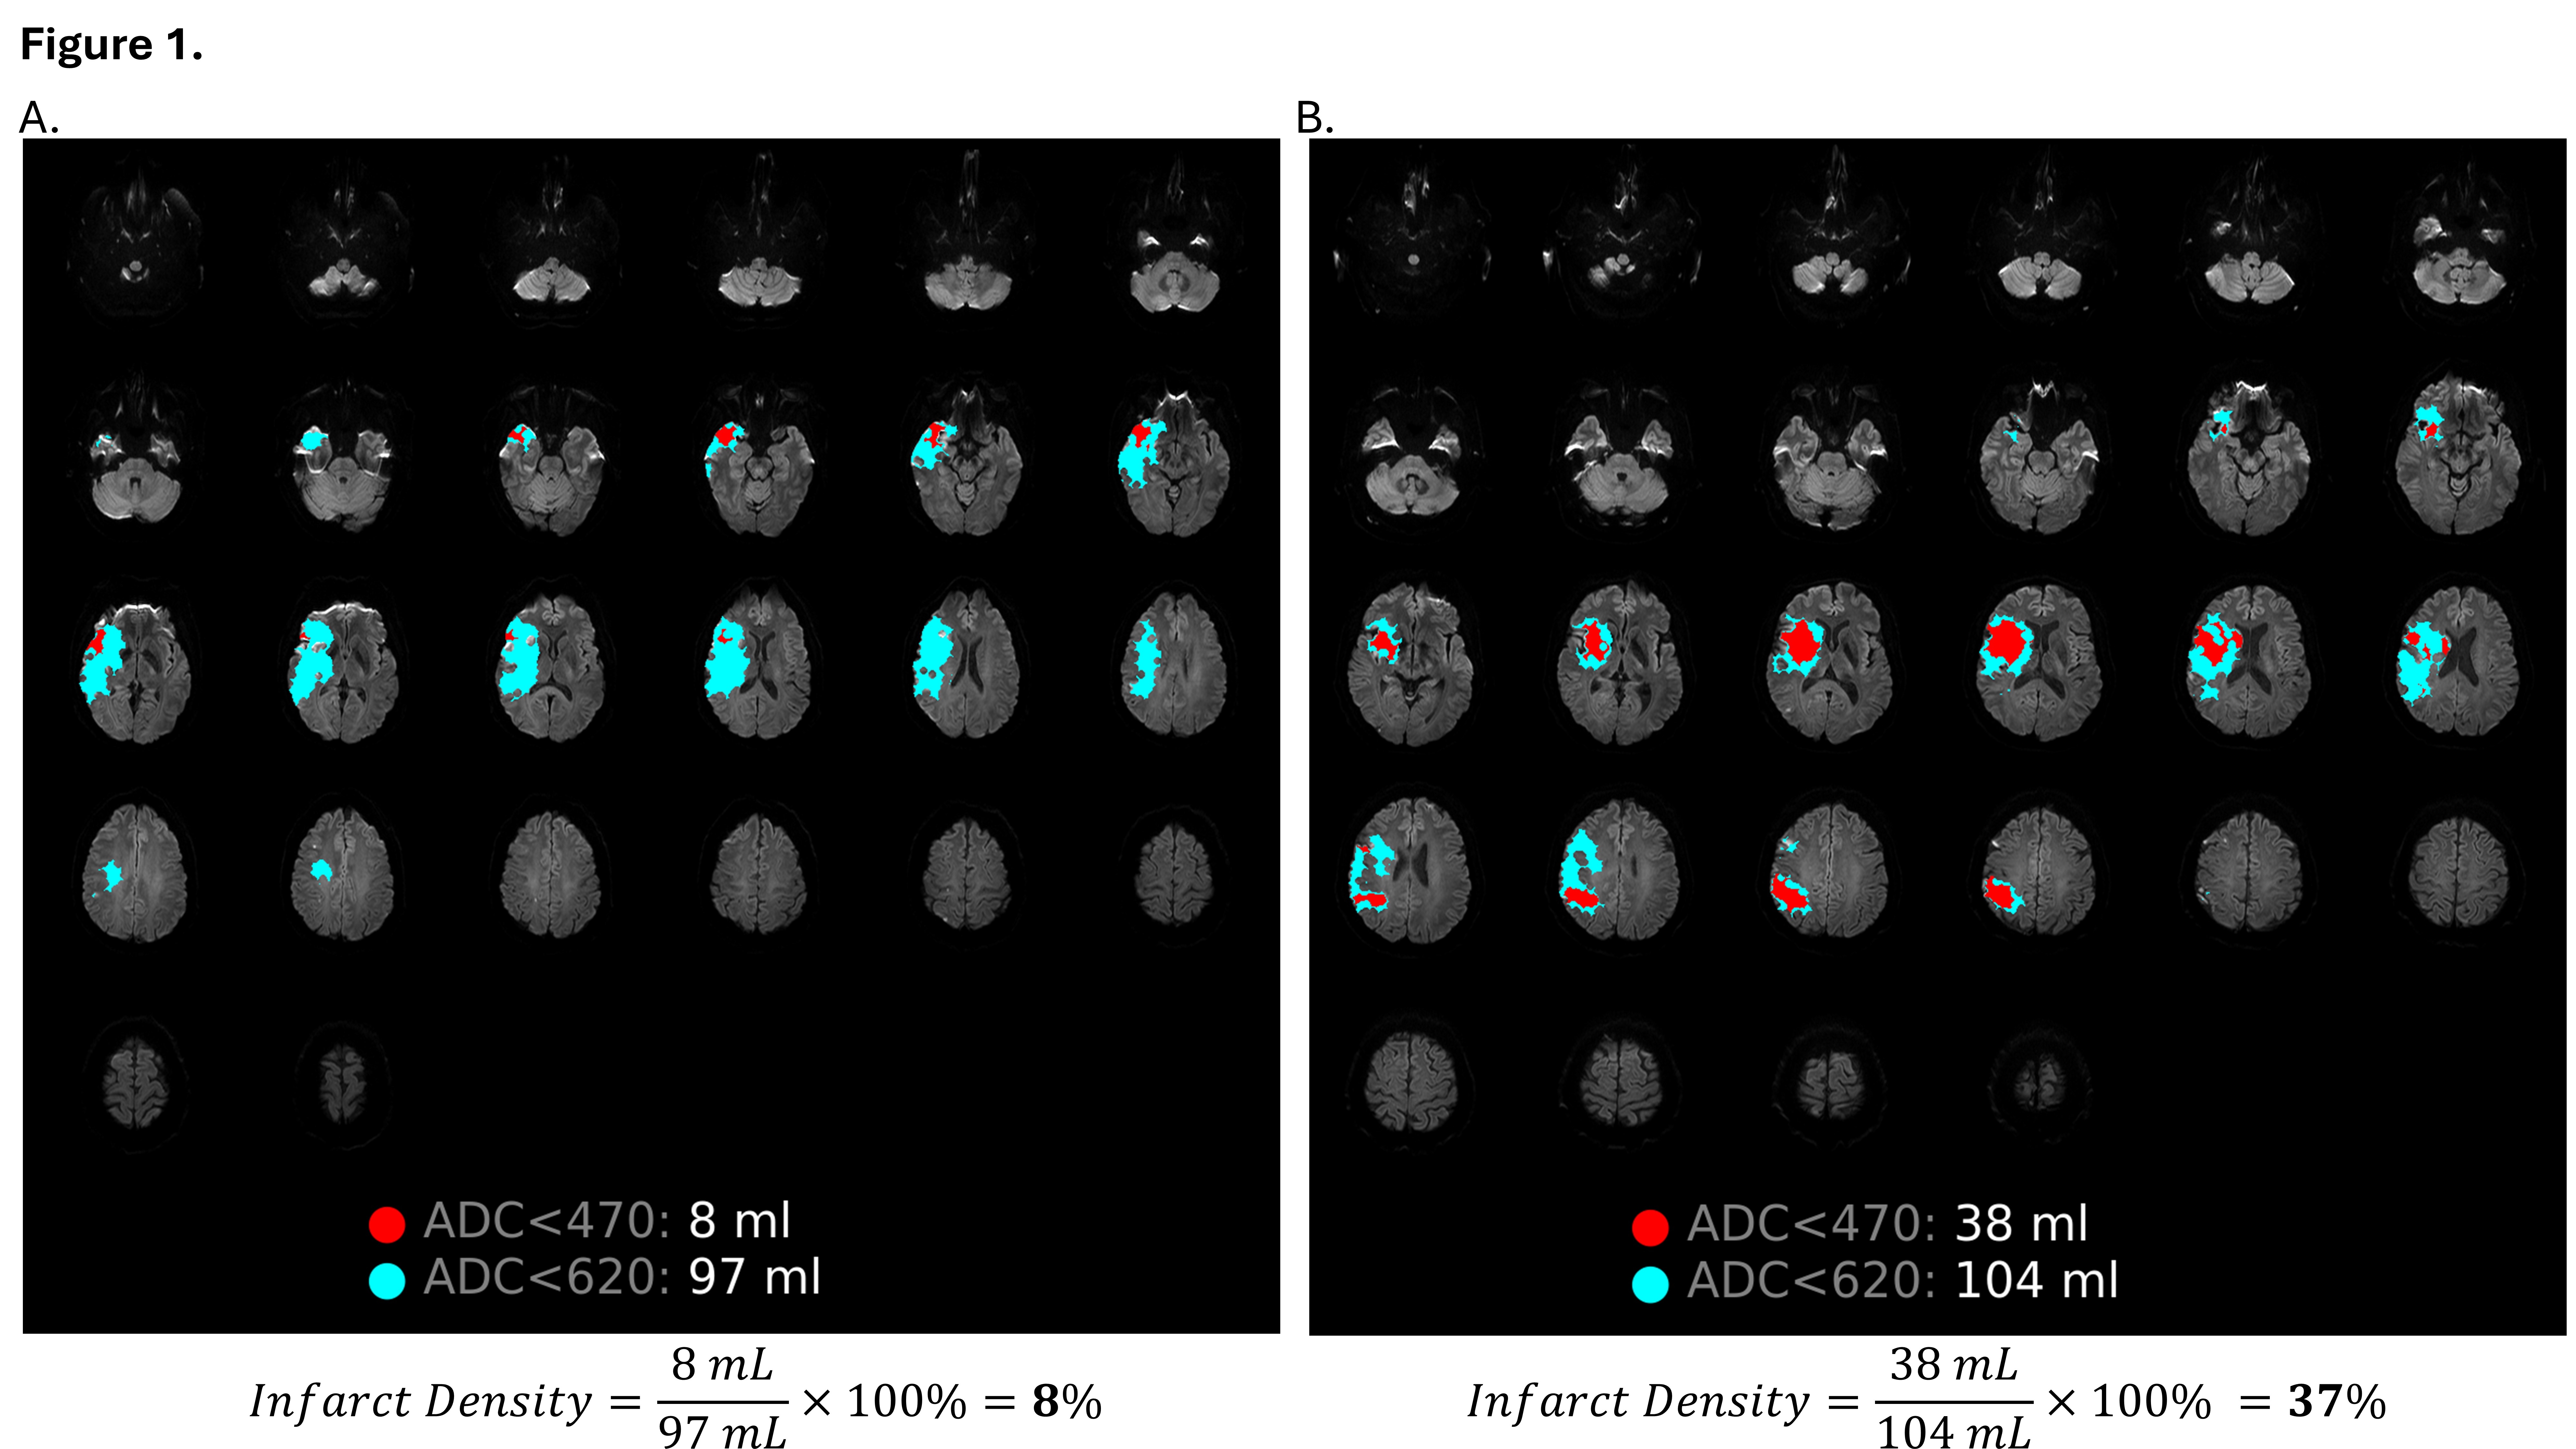

Methods: A retrospective cohort included consecutive patients with anterior circulation LVO who underwent EVT at two stroke centers. MRI was performed 12–48 hours post-EVT. Good functional outcome was defined as a 90-day modified Rankin Scale score ≤2. MR imaging was processed via RAPID, and final infarct volume was based on the standard ADC <620 threshold. Lesion volume was also assessed using ADC <470, and infarct density was calculated as the percentage of final infarct volume with ADC <470 (Figure 1). Multivariate logistic regression quantified the associations between clinical/imaging variables and functional outcome. Model performance was quantified by ROC analysis and compared to a model consisting solely of clinical variables and a model consisting of clinical variables and infarct volume.

Results: Of 312 patients, 284 (92%) achieved successful recanalization (mTICI ≥2b), and 54% achieved a good outcome. The mean age was 69 years (+/- 14); 41% were female. The mean final infarct volume was 50mL (+/- 73). Infarct density was significantly lower in patients with a good outcome (8.3% vs 30.3%, p<0.0001). Table 1 reports the univariate and multivariate analyses. Infarct density was robustly associated with outcome after adjustment for other significant factors including infarct volume (aOR: 0.954 per 1% increase in infarct density). Figure 2 compares the AUC of the three prespecified models, and the best classification was achieved by including infarct density (AUC 0.87; 95%CI: 0.83-0.91).